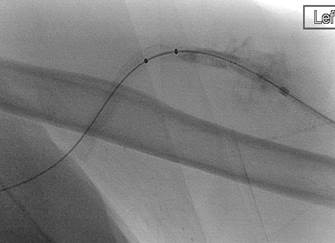

Catéteres DVX de AngioJet en injerto AV.

Imagen tras la activación del sistema AngioJet en el lado venoso del injerto AV.